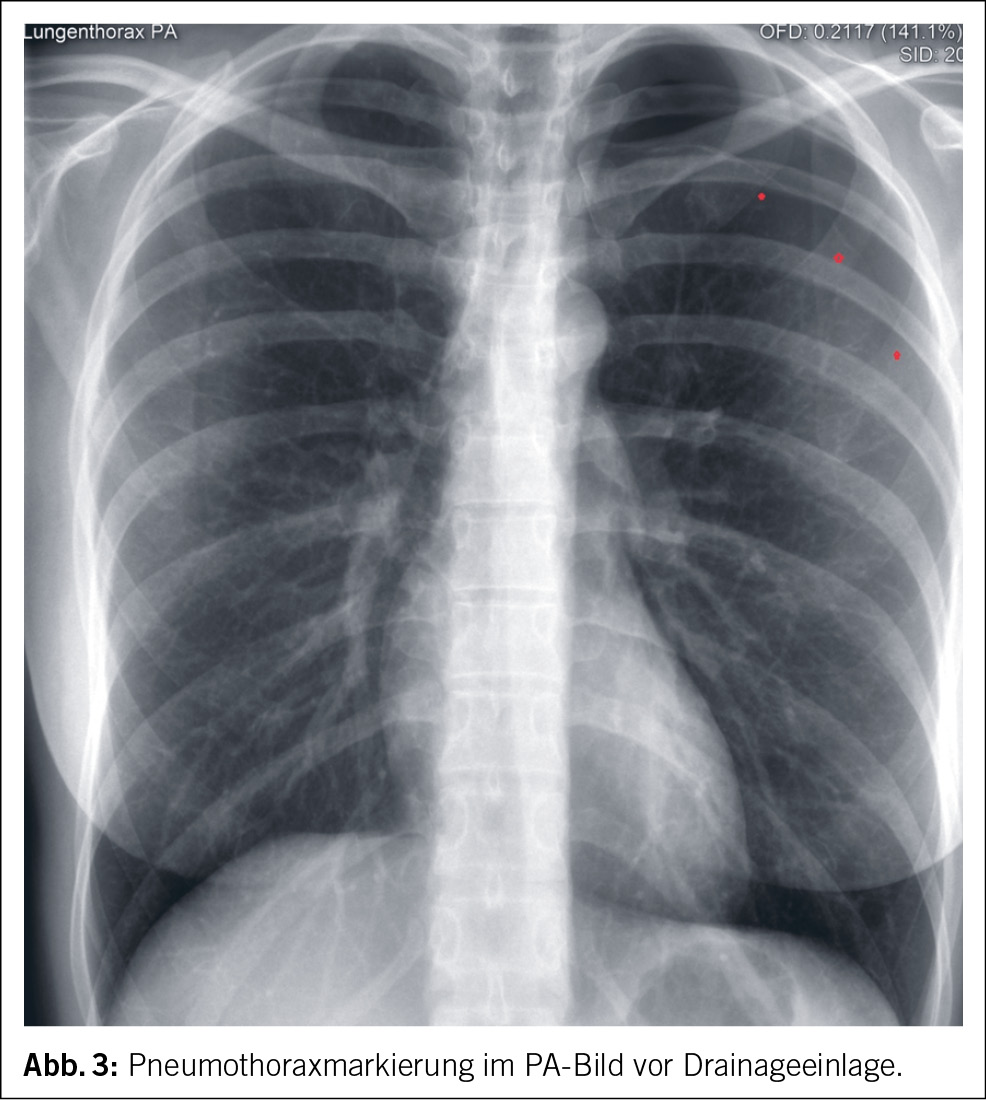

Ein Jahr nach der Diagnosestellung stellte sich die Patientin aufgrund akuter Beschwerden erneut bei ihrem Hausarzt vor. Sie berichtete über starke linksseitige Thoraxschmerzen, die sich beim tiefen Einatmen verschlimmerten. Es wurde eine Röntgenaufnahme des Thorax durchgeführt, das einen apikalen Pneumothorax von ca. 2 cm als passendes Korrelat für die Beschwerden zeigte. Die Patientin wurde notfallmässig ins Spital eingewiesen, wo sie stationär aufgenommen wurde. Zur Behandlung des Pneumothorax erfolgte die Anlage einer Thoraxdrainage (Abb. 3).